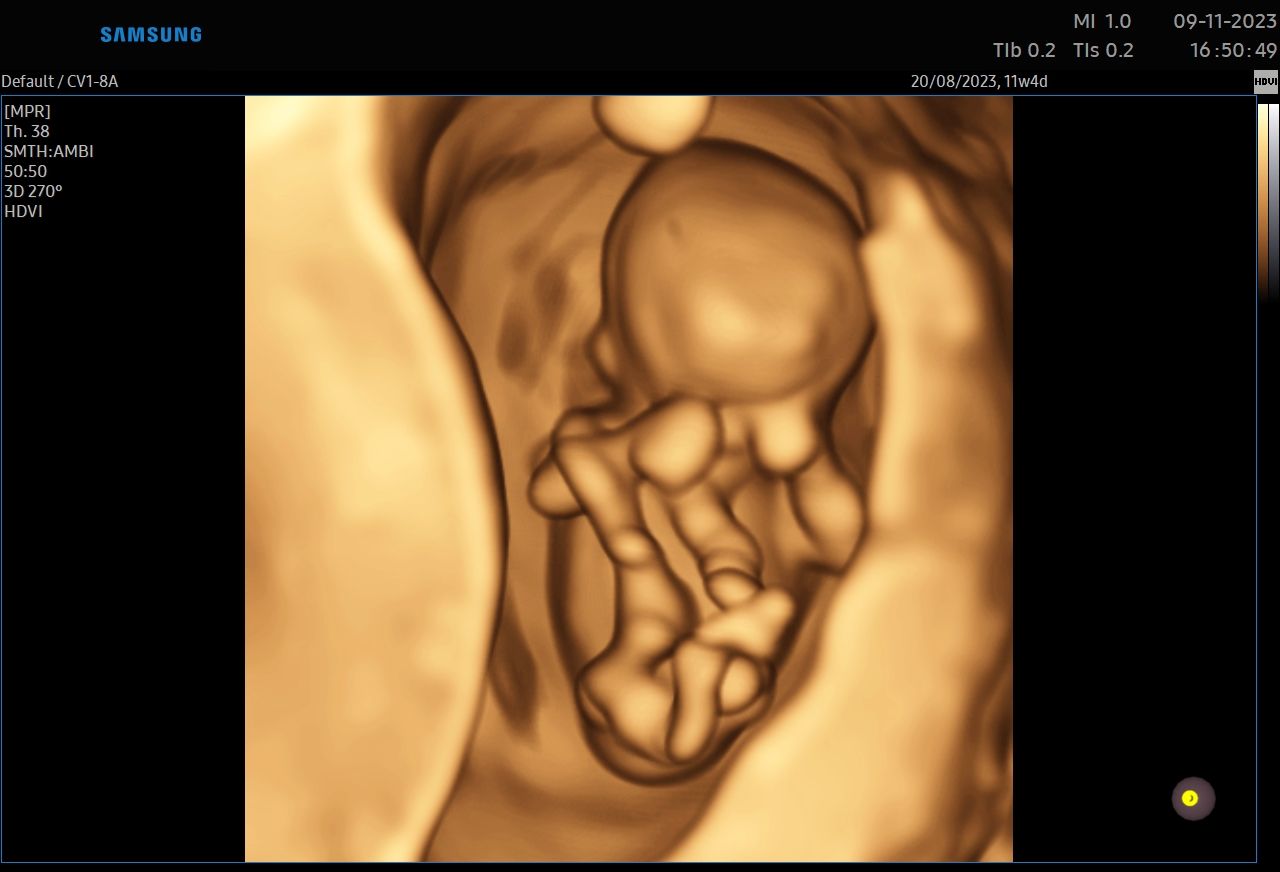

:-) Jestem lekarzem specjalistą w zakresie ginekologii i położnictwa , w ramach prowadzonej praktyki ginekologicznej staram się świadczyć kompleksowe porady lekarskie najwyższym poziomie ,w oparciu o najwyższe standardy jak i przy pomocy najnowszego sprzętu medycznego. W trakcie pracy zawodowej uzyskałem kolejno tytuły specjalisty I stopnia , a później specjalisty II stopnia , a także uzyskałem dodatkowe uprawnienia

CERTYFIKAT BADAŃ PRENATALNYCH POLSKIEGO TOWARZYSTWA GINEKOLOGÓW I POŁOŻNIKÓW

CERTYFIKAT BADAŃ PRENATALNYCH FMF ( FETAL MEDICINE FOUNDATION - LONDYN )

W ramach praktyki wykonuję pełen zakres badań ultrasonograficznych w zakresie ginekologii jak i położnictwa wraz z badaniami prenatalnymi , badaniami ultrasonograficznymi piersi .

Zdjęcia i filmy